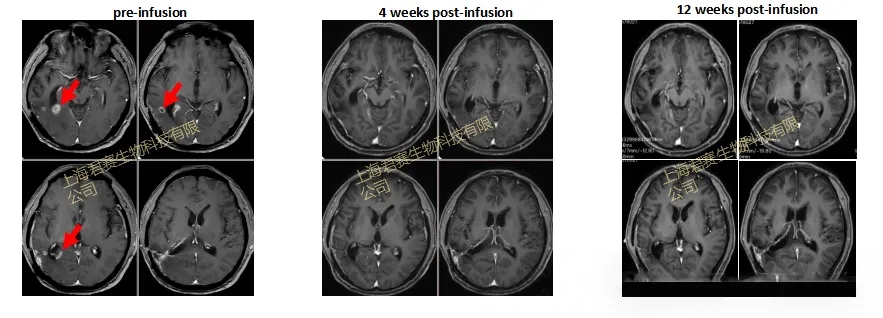

案例2(Ⅳ级脑胶质瘤):2025年SITC大会上,苏州大学附属第二医院与君赛生物联合公布I期临床试验(NCT04943913)振奋数据:一位确诊恶性程度最高的胶质母细胞瘤亚型的56岁男性患者,术后经Stupp方案、两次CAR-T治疗均失败。2023年末入组临床后,研究人员从其手术标本中制备TIL(T细胞占比99.92%,CD8⁺T细胞占比97.85%),12月完成输注。结果显示:GC101TIL细胞输注4周后,2.8cm复发病灶完全清零,疗效判定为完全缓解(CR);截至2025年6月,患者持续完全缓解超1.4年,已回归正常生活。

▲图源“JUNCELL”,版权归原作者所有,如无意中侵犯了知识产权,请联系我们删除